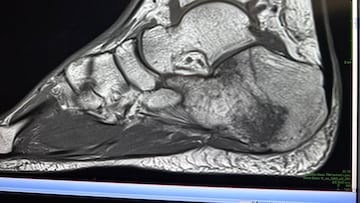

-Parecía que no era nada en las radiografías de Italia, lo que a mí no me parecía normal, porque yo he conducido con muchas lesiones y, sin duda, fue mi peor fin de semana a nivel de dolor en una moto de toda mi carrera deportiva. Lo pasé muy mal. No tenía nada de fuerza y no era capaz de utilizar el freno trasero. Me infiltraron muchísimo y no notaba mejora, así que el lunes me hice una resonancia y tengo dos fracturas del astrágalo y un edema óseo gigante, y distensión de los ligamentos. Realmente tengo el pie destrozado.